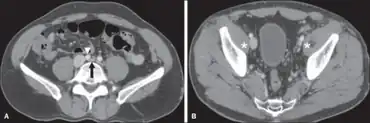

May-Thurner syndrome a)Compression of the left common iliac vein arrow by commoniliac artery arrowhead b) symmetry of externaliliac veins asterisk with diffuse tapering on left and ectasia on right

May–Thurner syndrome in the broader disease profile known as nonthrombotic iliac vein lesions (NIVLs) exists in the symptomatic ambulatory patient and these lesions are usually not seen by venography. Morphologically, intravascular ultrasound (IVUS) has emerged as the best current tool in the broader sense.[9] Functional testing such as duplex ultrasound, venous and interstitial pressure measurement and plethysmography may sometimes be beneficial. Compression of the left common iliac vein may be seen on pelvic CT.